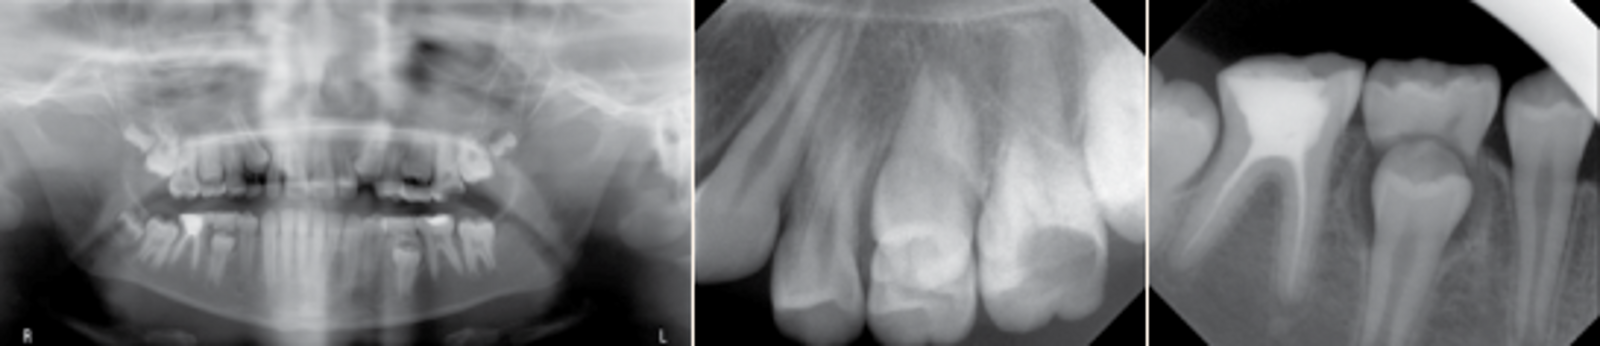

Radiographic investigations were done including (OPT and PA radiographs) to assess the proximity of the coronal defect to the pulp and to evaluate the periapical region and to ascertain the presence and stage of development of remaining permanent dentition (especially lower 7s, 5s and 8s).

MIH was diagnosed based on clinical appearance. See Figures 1 (a, b, c, d & e) for clinical features. Figures 2 (a, b & c) for radiographic findings.A diagnostic list and treatment plan was formulated by a specialist of Paediatric dentist as well as orthodontist and explained in detailed to the father.

Fig. 2 (a, b & c). OPT radiograph showing: normal alveolar bone levels, a normally developing dentition, except lower left third molar, E’s are near physiological exfoliation, more than 2/3 of the roots of 7’s are calcified, 46 RCT’ed, 36 composite restoration, 16.26 deep caries. PA radiograph showing: no signs of perapical radiolucency in lower and upper left first molars.